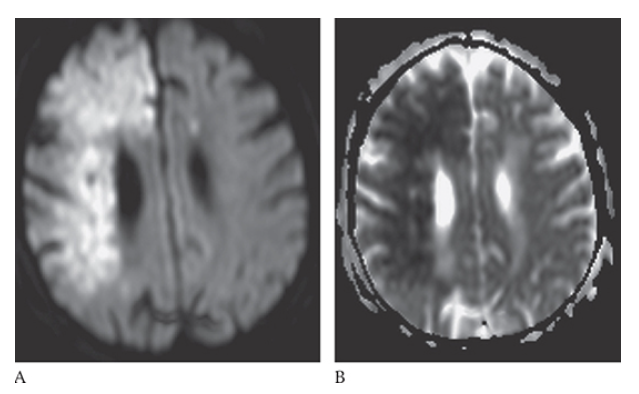

What is A

Ischemic Stroke. The portions of the area are bright on diffusion-weighted imaging but this is also bright on the apparent diffusion coefficient (ADC) map

What is B

Ischemic Stroke. The portions of the area are bright on diffusion-weighted imaging consistent with a subacute infarct.